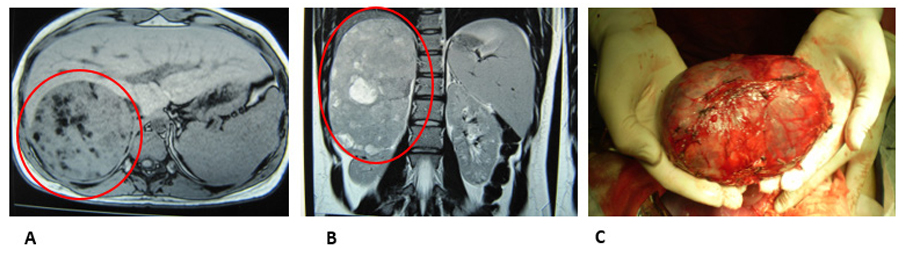

Adolescente de 16 años con antecedentes de pubarquia a los 3 años de edad, permanente y progresiva, con 6 años vello axilar, luego acné, seborrea y a los 11 vello facial. Luego clitoromegalia; negó cambios en la voz u otros elementos de hiperandrogenismo clínico. Consultó por amenorrea primaria. Al examen: peso 57 kg, talla 162 cm, hábito masculino. Acné severo en rostro y dorso, seborrea. Vello terminal en mentón, labio superior, axilas, línea infraumbilical, región sacra y muslos (Figuras 1A y 1B); escala de Ferriman-Galleway: 18. Mamas Tanner 1, clitoromegalia, vello púbico Tanner V (Figura 1C). Se palpó tumoración a nivel de hipocondrio y flanco derecho de 15 cm, dura, indolora. Laboratorio: testosterona total: 1478 ng/dl (6-82), testosterona libre: 26,08 mcg/mL (0,10- 3,20), DHEAS: 3590 mcg/dl (0-140), 17OH Progesterona 12,4 ng/ml (0,03-0,91). Cortisol basal, cortisol post 1 mg de dexametasona, ionograma normales. Ecografía ginecológica: útero adulto normal, endometrio 2 mm, ovarios: múltiples quistes. Tomografía (Figura 2A) que mostró voluminosa masa redondeada de bordes bien definidos, de 16 x 10 x 9,5 cm. Densidad sólida, heterogénea, con sectores hipodensos y calcificaciones; desciende y rota riñón derecho. Comprime y desplaza vena cava inferior. Hígado desplazado hacia adelante, sin alteración de la densidad hepática. No adenomegalias abdomino-pélvicas. RNM (Figura 2B): tumoración sólida suprarrenal derecha de 17 x 10 x 10 cm, con múltiples focos de grasa y algunas áreas sugestivas de necrosis o quísticas. Presentó realce inhomogéneo; contornos bien delimitados. Se realizó adrenalectomía derecha sin complicaciones. Patología, macroscopía: pieza de resección de 746 gramos, superficie externa lisa, completamente encapsulada (Figura 2C). Al corte, extensas áreas de necrosis y hemorragias; extensas áreas de calcificación. Microscopía: proliferación celular atípica pleomórfica que crece en patrón sólido trabecular, constituida por células grandes poliédricas, abundante citoplasma eosinófilo finamente granular (15% de células tumorales con citoplasma claro), núcleos pleomórficos con nucléolos con nucléolos evidentes e inclusiones intranucleares. Figuras abigarradas, mitosis típicas y atípicas. Múltiples focos de tejido hematopoyético. Se observan embolias a nivel vascular. En cuanto al índice mitótico, se observaron 30 mitosis por campos de gran aumento (CGA) con un Ki 67 del 12%. En suma: neoplasia primitiva suprarrenal maligna, con los caracteres de un carcinoma de corteza suprarrenal, criterios de Weiss 6 puntos. Al mes presentó disminución de clitoromegalia, a los 3 meses retomó ciclos menstruales mensuales y disminución del vello luego de depilación. A los 2 años de la cirugía se embarazó y tuvo un parto sin complicaciones. Desconocemos evolución posterior porque la paciente no volvió a consulta.

Figura 2: A) TC de abdomen (corte transversal): se observa masa suprarrenal derecha sólida, heterogénea, con sectores hipodensos y calcificaciones con bordes bien definidos, de 16x10x10 cm (círculo rojo). B) RM de abdomen (corte sagital): se observa la misma tumoración sólida (ovalo rojo) con realce inhomogéneo, contornos bien delimitados, algunas áreas sugestivas de necrosis. C) Pieza de resección: adrenalectomía con superficie externa lisa, completamente encapsulada.